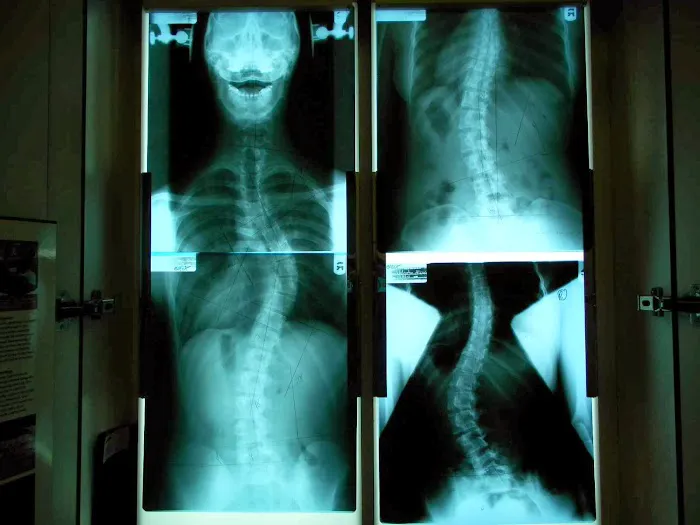

Strauss Scoliosis Correction Photos

The clinic’s reputation is built on successful outcomes and a patient-centric philosophy. Many patients have shared compelling stories of significant improvement, with some experiencing remarkable reductions in spinal curvature. This level of success, particularly with a condition often deemed "untreatable" by some traditional medical circles, highlights the unique expertise and dedication found at Strauss Scoliosis Correction. For residents of New York who may feel overwhelmed by the vast healthcare landscape, finding a specialized practice that delivers tangible results and compassionate care is a true asset. Dr. Strauss and his team strive to create an environment where patients feel understood, supported, and empowered throughout their healing journey.

For New Yorkers seeking highly specialized and effective chiropractic care, particularly for scoliosis, Strauss Scoliosis Correction in Nanuet, NY, stands out as an exceptional choice. The rave reviews from patients like Marin Ramos and the anonymous parent of a daughter whose curve significantly improved from 38 to 16 degrees, underscore the clinic’s profound impact on lives. These testimonials speak volumes about Dr. Strauss’s deep knowledge, customized treatment approach, and genuine care for his patients. As one parent noted, the notion that scoliosis cannot be treated is often misleading, and Dr. Strauss provides a powerful counter-narrative through his successful outcomes.

Jul 03, 2024 · Marin Gregorio Ramos MerinoMy daughter was diagnosed with scoliosis and we were told there’s no cure. It’s a crucial moment for any parents. Gratefully we found Dr. Strauss online. Amazingly after two weeks intense treatments, my daughter’s curve is corrected from 38 to 20 degree! And now her curve is reduced to 16. Dr Strauss is extremely knowledgeable. He effectively customizes treatment for each of his patients. On top of his expertise, Dr Strauss and his team also give patients and their families mental support. We highly appreciate Dr. Strauss who helps my daughter significantly corrected the curve! I also want to take the moment to spread the information that it is NOT true that scoliosis cannot be treated. I hope one day the official medical guidance for scoliosis can be modified. At least patient should be made aware of the option of being treated by Doctors such as Dr. Strauss.

Dec 13, 2024 · Frimet FrankelI started going to Doctor Strauss scoliosis correction a few months ago. I’m 34 and so my spine is less malleable therefore I didn’t expect how much improvement I found. The staff are very sweet and helpful. Leila was one of my favorite technicians. Heather was so helpful with making my appointments and handling the front desk responsibilities. Doctor Strauss is very professional and an expert at what he does. I was told in high school that I needed the serious surgery where they screw the rod into your spine to hold it straight. My fear kept me from following that path. At 32 I started having serious disc problems in my lower back and when I came for help this year I had a 49 degree C-curve and it is roto scoliosis. I came for 11 sessions and my degree of curvature went down to 36! My neck improved also. My pain went way down! I also participated in physical therapy at the same time which helped to keep me strong. Dr. Strauss designed an exercise program to lead to more success. He didn’t tell me I needed more sessions but I actually asked to do more because of how much better I feel in my daily activities. I feel like I’m getting my life back. Thank you Dr. Strauss and the team at the scoliosis correction center! I will be continuing on with you as long as I can afford!